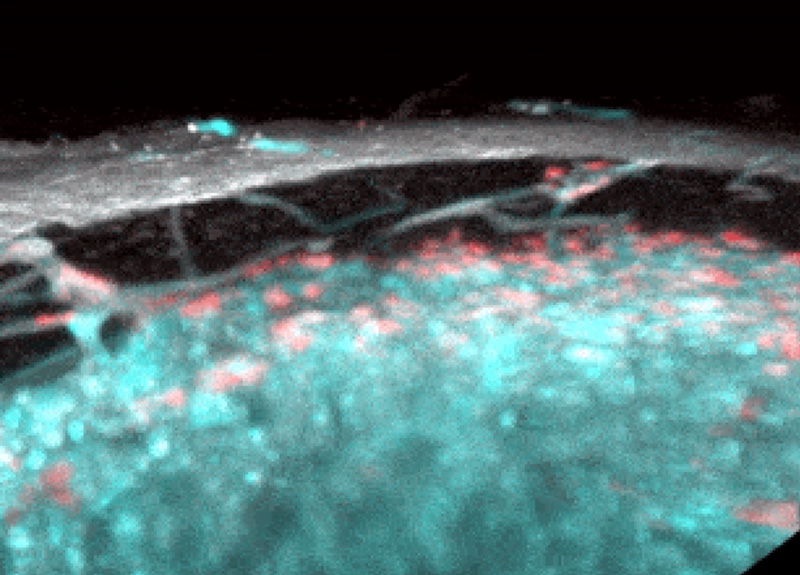

Estudiaron los huesos tibiales de ratones tratados con cinamato de etilo, que hace que los huesos sean más transparentes, utilizando microscopía de luz y microscopía de rayos X. Así, los investigadores vieron por primera vez que los vasos transcorticales más pequeños (TCV) pasaban a través de la sustancia ósea. Estos canales delgados están recubiertos con endotelio, como los vasos sanguíneos normales. Según los autores del estudio, el hueso tibial de un ratón puede ser penetrado por más de un millar de estos vasos. Alrededor del 80% de la arteria y aproximadamente el 60% de la sangre venosa que pasa a través del hueso se transporta a través de estos canales. Es decir, la mayor parte del intercambio entre la médula ósea y el sistema circulatorio pasa a través de ellos.

Diagrama de la estructura del vaso transcortical que pasa a través de la sustancia compacta del hueso largo. /Nature